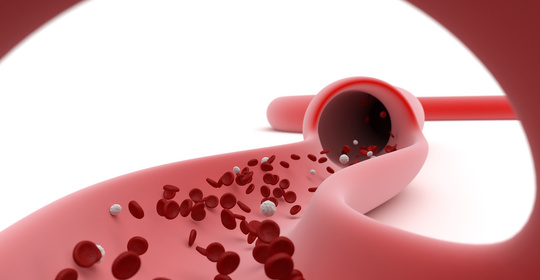

新生兒低血糖症與高血糖症:識別與有效干預

新生兒低血糖症:原因、診斷及急救措施

新生兒高血糖症:病因、症狀及治療新進展